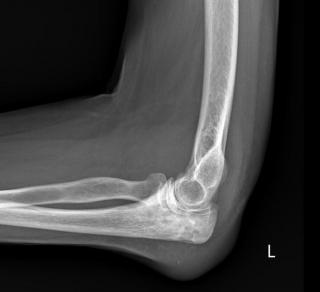

Инструментальные методы диагностики включают рентгенографию грудной клетки, однако на ранних стадиях костные изменения могут быть минимальными или отсутствовать. Рентгенологическая диагностика остеомиелита рёбер направлена на выявление прямых признаков воспалительно-некротического процесса в плоских костях грудной стенки, включая деструкцию кортикального слоя и перестройку губчатого вещества. Исследование проводится в прямой и косых проекциях в режиме обзорной рентгенографии с прицельной съёмкой поражённого сегмента грудной клетки.

Рентген выявляет следующие анатомические признаки:

- В прямой проекции визуализируется участок остеопороза в теле ребра с нарушением обычного трабекулярного рисунка, размытыми контурами и снижением плотности в зоне предполагаемого воспаления.

- В косой проекции определяется прерывистость наружного кортикального слоя с деформацией изгиба ребра и признаками периостального наслоения, образующего неравномерную теневую полосу вдоль диафиза.

- На прицельной рентгенограмме отмечается наличие секвестра — отдельного фрагмента плотной костной ткани внутри зоны остеолиза, окружённой зоной склерозирования и возможного периостального отслоения.

Рентгенографическое исследование позволяет детально визуализировать следующие диагностические параметры остеомиелита рёбер:

- Протяжённость и локализация зоны остеодеструкции, включая вовлечение диафизарной и паракостальной части ребра.

- Форма, размеры и плотность секвестра, позволяющие отличить зону некроза от реактивных костных изменений.

- Степень нарушения кортикального слоя и выраженность периостальной реакции с определением её распространения и конфигурации.

- Наличие склеротической каймы вокруг очага воспаления, отражающей стадию хронического процесса.

- Сопоставление положения очага с соседними анатомическими структурами грудной клетки, включая мягкие ткани.

Рентгенологическое обследование ребер имеет ряд ограничений, и с его помощью не всегда удаётся точно визуализировать следующие аспекты:

- Начальные воспалительные изменения без деструкции костной ткани могут не проявляться в течение первых 10–12 суток.

- Слабовыраженные перестройки в губчатом веществе рёбер при поверхностном распространении инфекции могут быть неразличимы на фоне плотности грудной стенки.

- Оценка состояния прилежащих мягкотканевых структур, включая мышечную и жировую клетчатку, недоступна в рамках проекционного метода.

- Интраструктурные гнойные полости и небольшие каналы секвестрации остаются за пределами визуализации при стандартных режимах съёмки.

- Присутствует лучевая нагрузка: при выполнении рентгенографии грудной клетки в прямой и косых проекциях с прицельной съёмкой поражённого ребра суммарная эффективная доза составляет от 0,2 до 0,5 мЗв.

Более информативной является компьютерная томография ребер, позволяющая визуализировать участки остеолиза, секвестрации, периостальную реакцию, разрушение кортикального слоя рёбер и наличие парарёберных абсцессов. Магнитно-резонансная томография грудной клетки позволяет оценить распространение воспалительного процесса на мягкие ткани, визуализировать отёк костного мозга, свищевые ходы и области инфильтрации. В хронических случаях возможно применение остеосцинтиграфии с технецием-99m для определения метаболически активных очагов воспаления.